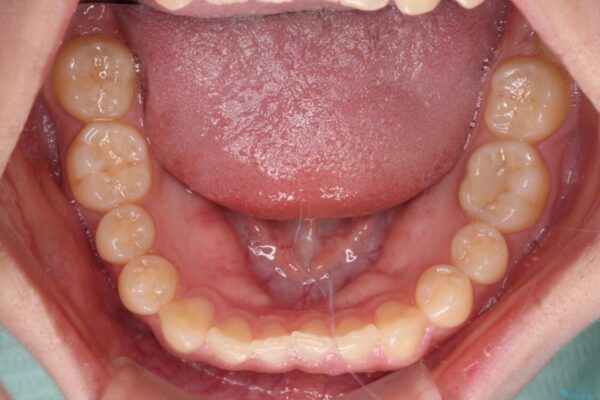

治療前

• 治療途中の奥歯と矯正治療の後戻り インビザライン・ライトによる矯正治療 治療前画像